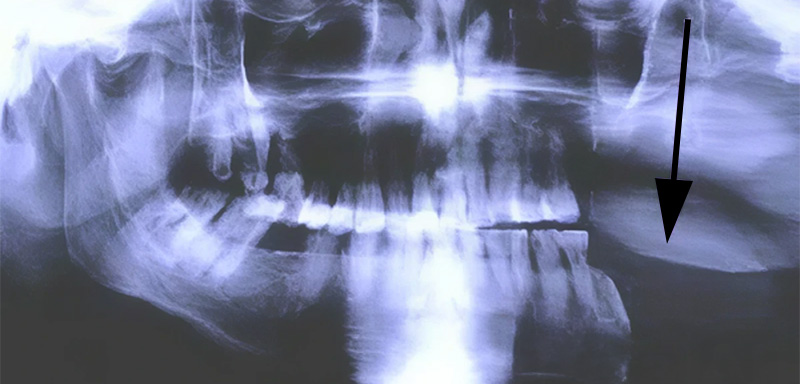

Fig. 02.

Indications tissus durs associés aux tissus mous au maxillaire :

Cette chirurgie s’adresse aux tumeurs du sinus maxillaire et aux carcinomes épidermoïdes nés de l’infrastructure. Cette exérèse concerne en général l’hémi section ou la section totale du maxillaire avec une partie plus ou moins importante du voile mou. Elle met en relation directe le rhinopharynx et le plancher de l’orbite avec la cavité buccale.